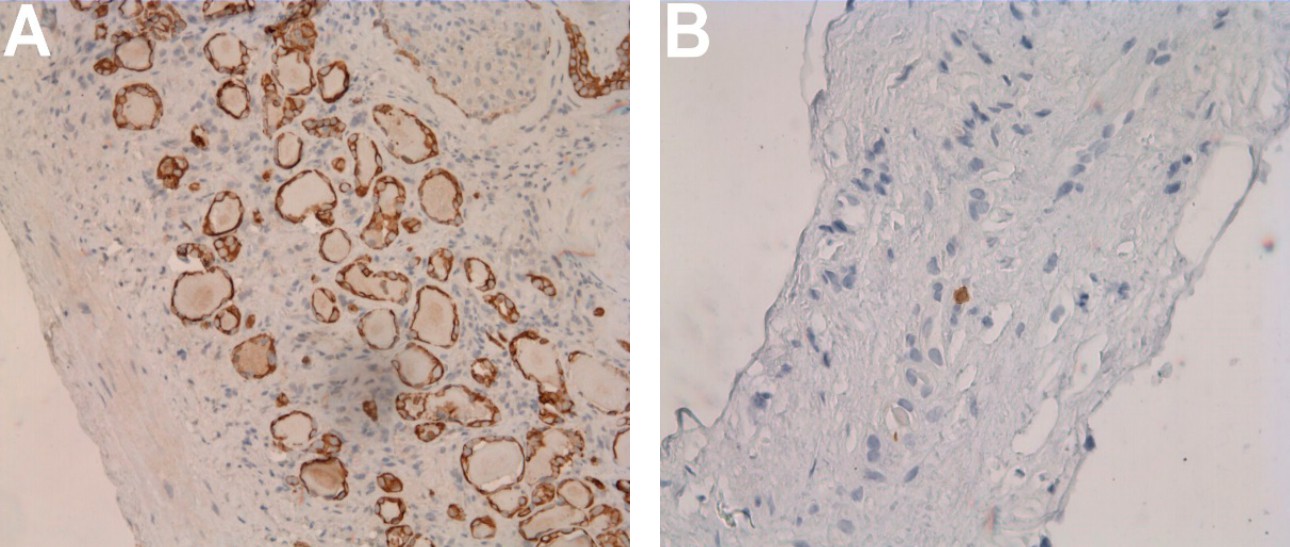

Pathology result

Despite the fact that there were no signs of malignancy for the renal cystic mass, the patient insisted on surgery. The cystic mass of the right kidney was resected at the Republican Clinical Oncological Dispensary of the Ministry of Health of the Republic of Tatarstan named after Professor M.Z. Sigal. Finally, the histological examination confirmed a simple renal cyst (Figure 7).

Ultrasound examination is the most common method for visualizing the kidneys. With B-mode ultrasound, usually it is easy to differentiate a simple cystic mass. But sometimes it is difficult to differentiate complex cysts from malignancy, even with Doppler imaging. However, the introduction of ultrasound contrast agents into clinical practice has significantly improved the diagnostic efficiency of ultrasound. CEUS is very useful in the further assessment of uncertain cystic renal mass as it can show whether there is enhancement or not [1,2,3]. In this study, power Doppler was used to evaluate for internal flow with indeterminate results. But CEUS demonstrated that there was no enhancement within the complex cystic mass and the mass was characterized as benign. Finally, the postoperative histological examination confirmed the same diagnosis. Therefore, CEUS is very helpful for non-invasive characterization of complex cystic renal mass and may help patients avoid surgery.